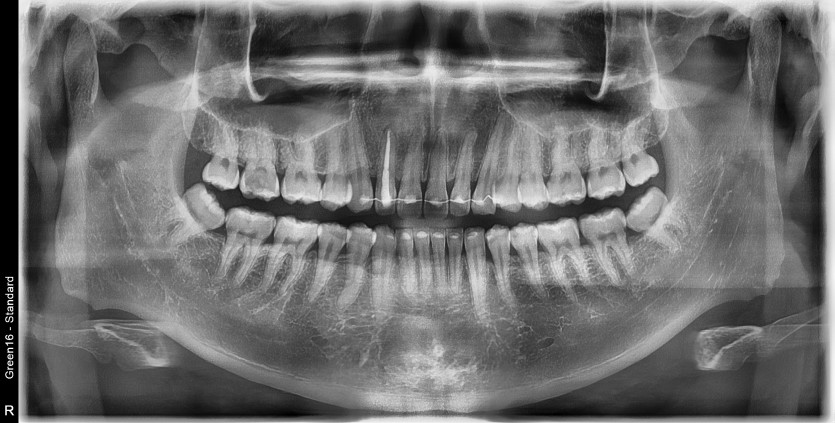

#18,48 사랑니 발치

구강 외과 전문의가 당일 발치했습니다.